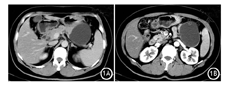

患者女性,48岁。因发现上腹部肿块10 d入院。既往有2型糖尿病、高血压、乙型肝炎疾病史。腹部超声见胰尾部64 mm×32 mm液性暗区,边界尚清;腹部CT示胰尾部囊肿,边界清,大小为8.3 cm×6.2 cm,增强后未见强化(图1);左肾囊肿。实验室检查:CEA 5.13 ng/ml,CA19-9 530.30 IU/ml,其余生物化学指标未见异常。择期剖腹探查,术中见胰尾部一囊性肿块,活动度可,与周围组织分界清,行胰体尾+脾脏切除术。切除标本大体见约8 cm×8 cm×8 cm肿块,壁厚,包膜完整。术中快速冷冻切片提示胰体尾部浆液性囊腺瘤,术后病理检查见胰尾部上皮性先天性囊肿伴感染及组织细胞反应(图2);慢性淤血性脾肿大伴包膜下出血,脾门淋巴结炎。诊断:先天性胰腺囊肿。